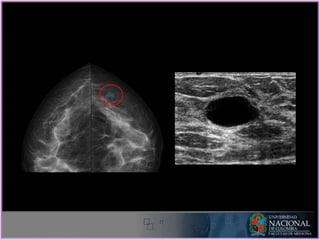

Indicaciones:

2. Prueba complementaria:

• Caracterizar alteración mamográfica (90 % diferencia

quístico de solido).

• Valorar alteración identificada en una sola proyección

mamográfica.

ECOGRAFIA - Indicaciones Indicaciones: 2.Prueba complementaria: • Caracterizar alteración mamográfica (90 % diferencia quístico de solido). • Valorar alteración identificada en una sola proyección mamográfica.